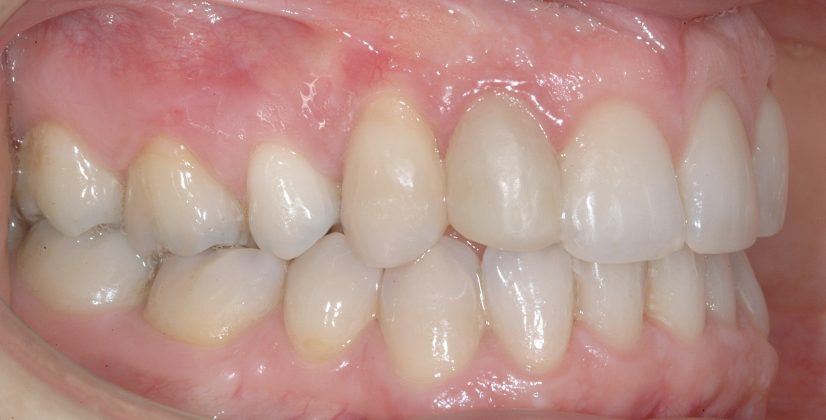

Una paziente di sesso femminile, 38 anni, già trattata ortodonticamente presso altra sede con apparecchiatura fissa a entrambe le arcate in età adolescenziale senza successiva applicazione di alcuna contenzione, si presenta alla nostra attenzione perché insoddisfatta dell’estetica del sorriso; richiede una valutazione per un trattamento ortodontico con apparecchiatura fissa linguale per la presenza di affollamento dentale a entrambe le arcate e difficoltà a mantenere una adeguata igiene orale; si riscontrano agenesia di entrambi gli incisivi laterali superiori (1.2 e 2.2) e del secondo premolare inferiore destro (4.5). Presentiamo la risoluzione del caso mediante trattamento ortodontico estrattivo a entrambe le arcate, eseguito con apparecchiatura linguale invisibile 2D e meccanica asimmetrica e seguito a medio termine da riabilitazione implanto-protesica e contenzione fissa.

Per formulare corretta diagnosi e piano di cura, lo studio del caso ha previsto la raccolta di documentazione completa standard, ovvero fotografie del viso e intraorali (Figure 1a-e), radiografia panoramica e teleradiografia del cranio in proiezione laterale (Figure 2a-b) per la relativa analisi cefalometrica e modelli di studio.

La valutazione clinica e gli esami effettuati confermano la presenza di agenesia degli incisivi laterali superiori (1.2 e 2.2) e del secondo premolare inferiore destro (4.5).

L’analisi ortodontica e la valutazione parodontale, con particolare riferimento alla posizione della radice del canino superiore destro (1.3), distoinclinata e trasposta alla radice del primo premolare (1.4) come evidente dalla radiografia panoramica e dalle immagini intraorali, ci hanno guidati nella programmazione di un trattamento estrattivo asimmetrico a entrambe le arcate.